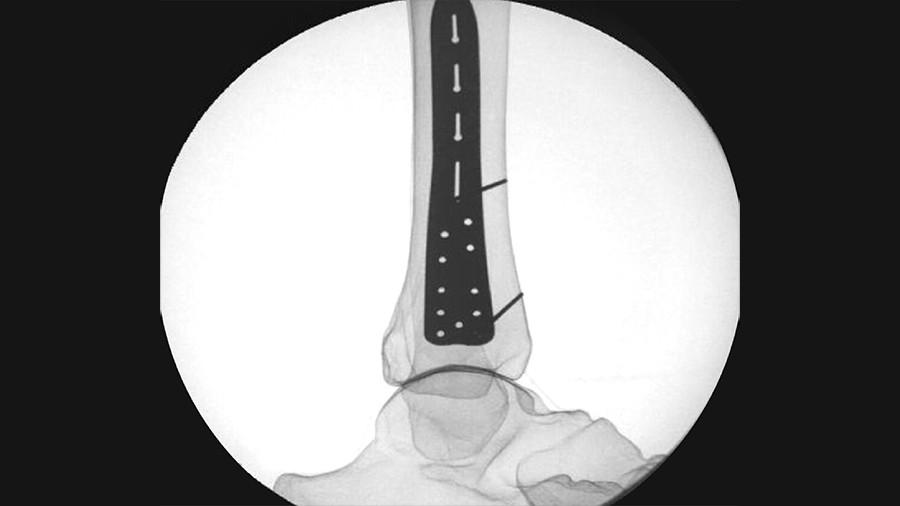

DePuy Synthes Hammertoe Continuous Compression Implant

Hammertoe deformities are one of the most frequent deformities treated by foot and ankle surgeons. In rigid and structured hammertoe deformities not suited for nonoperative management, arthrodesis of the proximal interphalangeal (PIP) joint represents the standard treatment. Temporary K-wire fixation is the most frequently used, low-cost fixation method for PIP joint fusion. However, reported complications associated with K-wires have prompted the development of new implants over the past decade. To address weaknesses of intramedullary fixation concepts (eg, limited rotational stability), the Foot and Ankle Expert Group approved the first extramedullary continuous compression implant (CCI) to treat hammertoe deformities – the DePuy Synthes Hammertoe Continuous Compression Implant (DPS Hammertoe CCI).

The DPS Hammertoe CCI has a staple-like design with four legs and a low profile connecting bridge (Fig 1). It is made of biocompatible Nitinol, a metal alloy of nickel and titanium, which is known for its superelastic properties and shape memory behavior.

Once the DPS Hammertoe CCI is inserted into the bone and released from the Insertion Stick, the implant attempts to regain its original shape with converging legs thereby providing active continuous compression at the fusion site (Fig 4). The design with the four legs orthogonal to the bone axis and the active compression feature are beneficial for the distraction resistance (Fig 5).